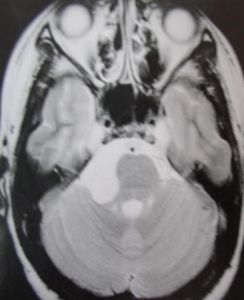

2.MR表現:

①鞍上池或橋小腦角池類圓形或不規則病變,邊緣銳利。

②T1加權絕大部分為均勻的低信號,少數由於瘤體內含液態膽固醇或出血而呈高信號影。T2加權呈明顯的、均勻一致的高信號影,高於腦脊液信號。

③腫瘤包膜於T1加權呈中等信號,T2加權呈高信號影。

④增強檢查無強化效應。